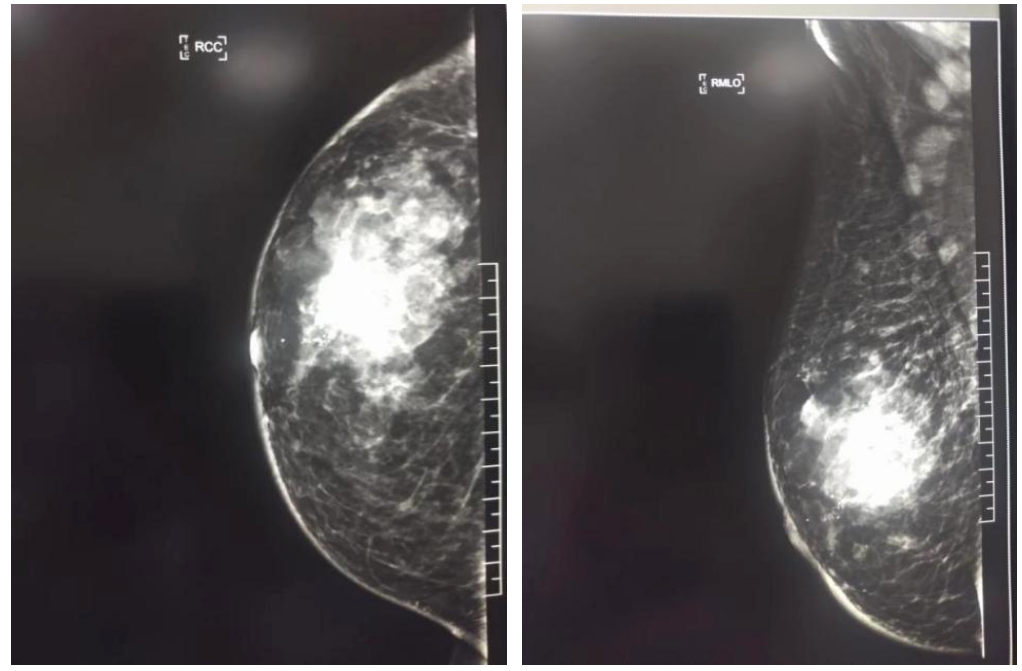

2021年12月10日,乳腺核磁影像表现:左乳明显变形,其内可见多发结节及肿块影,大小不等。最大者约6.3×4.8×5.1cm。形态不规则,信号不均匀,边缘可见分页周围腺体结构紊乱。累计临近皮肤,皮肤明显不规则增厚。

诊断:1、右乳恶性肿瘤(多灶),局部累及皮肤伴右腋下淋巴结转移(BI-RADS:6)。2、左乳腺体增生。3、左腋下多发小淋巴结。

图2.双侧乳腺核磁